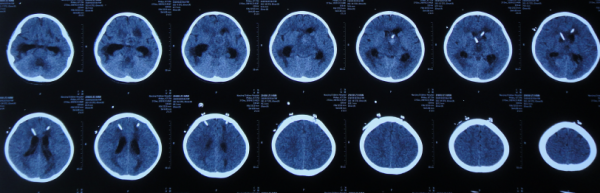

入院次日即2019年12月12日,進行了腦室外引流術,術後次日查頭部CT(圖-5)。

圖-5:2019年12月13日頭部CT

第2家醫院治療3天即2019年12月14日(腦室引流術後第2天),術後腦室引流不暢,查頭部CT示右側腦室擴張加重(圖-6)。

圖-6:2019年12月14日頭部CT

第2家醫院治療4天即2019年12月15日,進行了顱內壓力感測器腦室內植入術+右側腦室外引流術(圖-7)。

圖-7:2019年12月15日頭部CT

但術後次日即第2家醫院治療5天即2019年12月16日,出現高熱,腦脊液培養陽性(產酸克雷伯菌),給予加強抗感染治療,聯合鞘內注射藥物治療,但頭部CT示腦室縮小(圖-8)。

圖-8:2019年12月16日頭部CT

第2家醫院繼續治療8天時間內,期間4次查頭部CT示腦室逐漸再次擴張(圖-10、圖-11、圖-12、圖-13)。

圖-10:2019年12月18日頭部CT

圖-11:2019年12月19日頭部CT

圖-12:2019年12月22日頭部CT

圖-13:2019年12月25日頭部CT